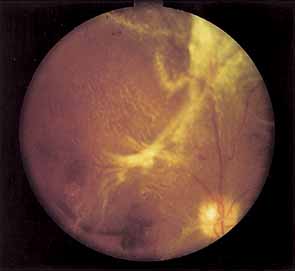

PROLIFERATIVE DIABETIC RETINOPATHY

Proliferative vessels usually arise from veins and often begin as a collection of fine vessels. When they arise on or within 1 disc diameter of the optic disc they are referred to as neovascularization of the disc (NVD) (Fig. 9). When they arise further than 1 disc diameter away, they are called neovascularization elsewhere (NVE) (Fig. 10). NVE nearly always grows toward and into zones of retinal capillary nonperfusion, but capillary nonperfusion is nearly always more widespread in eyes with NVD than it is in NVE.12 Interestingly, it is seen more often in patients younger than 40 compared to older patients with diabetes.13

Fig. 9 Advanced neovascularization of the disc.

Once the stimulus for growth of new vessels is present the vessels grow along the path of least resistance. The absence of the internal limiting membrane over the optic disc could explain the proclivity of new vessel growth at that location. Neovascularization grows readily along connective tissue scaffolding such as the posterior hyaloidal face (Fig. 11).